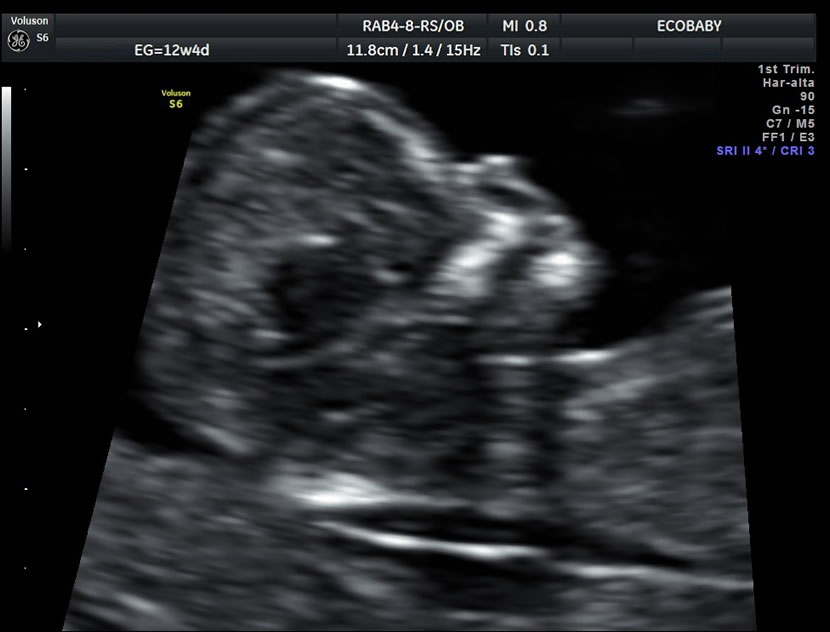

- Una ecografía entre las semanas 11-13.6 de embarazo:

> Para medir el grosor de líquido detrás de la nuca del feto (translucencia nucal)